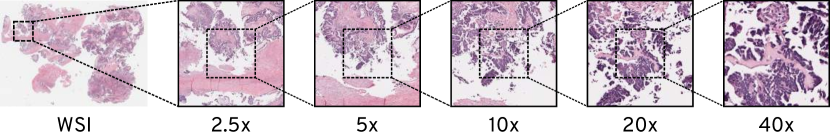

We used publicly available data from The Cancer Genome Atlas (TCGA). An important characteristic of this dataset is the available objective power of the whole slide images, which represents different magnification levels. Other publicly available datasets like PMC do not contain magnification information, making them unsuitable for this study. Each image was stored at various magnification levels and in a pyramid structure. The subset from the original dataset was created using an indexing algorithm, which would randomly index one whole slide image (WSI) at a time. If the objective power(i.e., the magnification of base layer) of 40x or 20x was absent, we discarded that WSI. In total, we gathered 29,596 WSIs for creating our magnification specific dataset. For these WSI files we randomly selected the coordinates of 5 points, read the image at respective magnifications from that specific coordinates and took a snapshot at each point. This yielded us the total of 693,518 patches, consisting of 147,477 patches at 2.5x,5x,10x and 20x and 103,611 at 40x. A region of a sample snapshot at different magnification levels is represented in Figure 1.